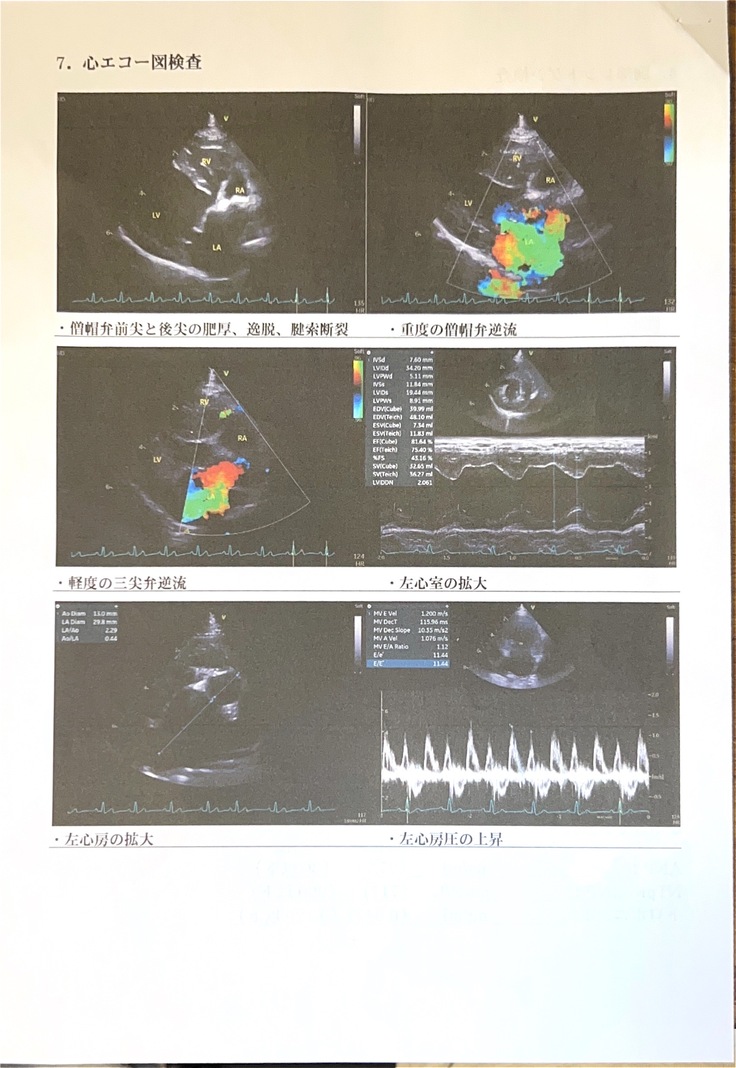

8月に行った心臓ドックの結果、左心房・左心室の拡大と三尖弁の逆流(軽度)がみられました。

↓8月の心臓ドック結果報告内容